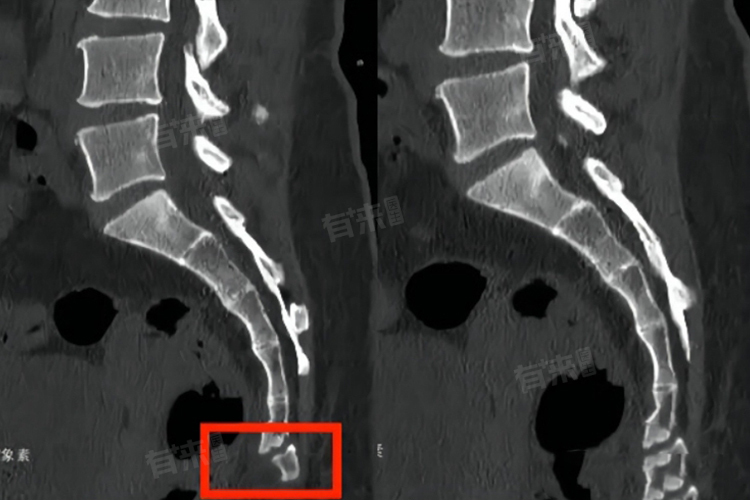

骶5椎体骨折的完全恢复时间取决于骨折类型、骨折移位程度、个体身体素质、治疗措施以及康复训练等因素,一般在6周到6个月左右,患者应积极配合治疗,按照医生的建议进行康复训练,以促进骨折的愈合和身体功能的恢复。

2、骨折移位程度:若骨折明显移位,甚至损伤了周围的神经、血管等组织,恢复时间会大大延长。患者可能会出现下肢麻木、疼痛、大小便功能障碍等症状,可能需要8-12周的卧床休息,4-6个月才能完全恢复正常。

4、治疗措施:保守治疗包括卧床休息、佩戴支具等。采取保守治疗且骨折较轻的患者,恢复时间通常在8-12周。如果骨折严重,需要手术治疗,术后可能需要12-16周的康复期,才能完全恢复。